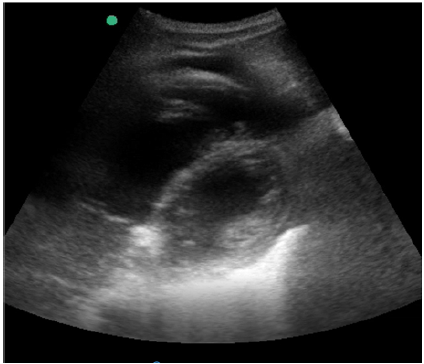

Então, decidiu-se realizar um ecocardiograma beira-leito, cujo resultado é a imagem mostrada a seguir na janela paraesternal eixo curto.

De acordo com essa imagem, a hipótese diagnóstica principal é